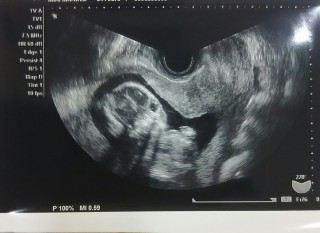

写真:15w2d:ななさん

初経腹エコーでした! 心臓も背骨もばっちりでしたが、性別は次回に持ち越しです;; BPDは33.2、CRLは10.57で1か月前のほぼ倍の大きさに…! ちなみに4Dエコー中赤ちゃんは胎盤?と思しき壁をバンバン叩いており、 この子が今後大きくなったら痛いだろうな、、、と覚悟を決めました(笑)